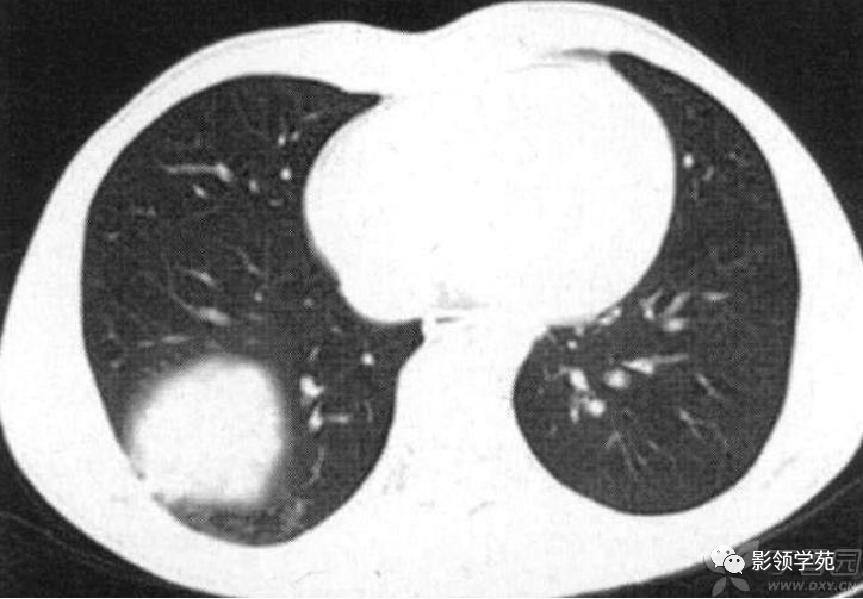

胸部CT检查有阳性发现者占97%,包括多发性肺结节、肿块、楔形病灶、片状浸润阴影、空洞、气道狭窄或溃疡、肺出血等。肺部Wegener肉芽肿CT征象多样,典型的影像学特点是“三多”,即多发性、多样性、多变性。多发性指肺内多处病变,散在双侧肺野,尤以双下肺好发。多样性指病变形态及新旧不一,病变形态多样,呈结节、实变、空洞及条索影等,结节及空洞较为常见。空洞形成是Wegener的重要影像特点,环形空洞是此病的特征。浸润、空洞及结节等多种形式常同时存在。多变性指病变部位、大小及形态处于动态变化之中。

肺内多发结节和肿块是肺Wegener肉芽肿最常见的影像征象,表现为两肺散在分布、多发大小不等类圆形结节或肿块影,以两肺中下野分布多见。部分结节和肿块内可见空洞,洞壁多较厚,内缘光滑或不规则,空洞呈边缘性强化。合并感染时空洞内可形成液-气平面。结节或肿块周围一般都有较短毛刺,部分病灶有长毛刺与邻近的胸膜相连,表现为胸膜凹陷征。这与病理上结节周围存在大量成纤维细胞以及以纤维化形式愈合有关。

病例8:右上肺胸膜下病灶,伴厚壁空洞,邻近胸膜楔形增厚。